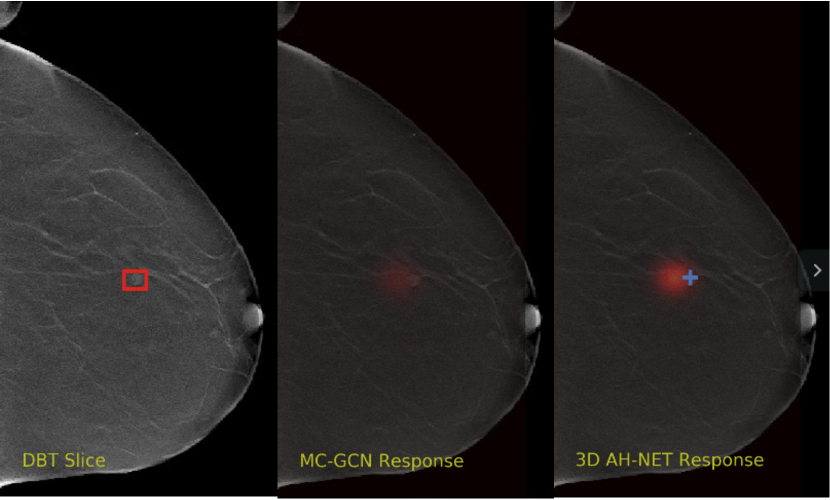

Refer to caption

Figure 5: The visual comparisons of the network responses on 2 different DBT volumes from 2D GCN and the 3D AH-Net with the encoder weights transferred from it. Each volume is visualized with the maximum intensity projection of the xy𝑥𝑦xy plane (top-left), the xz𝑥𝑧xz plane (bottom) and the yz𝑦𝑧yz plane (right). The ground truth lesion centres are shown on the left. With the additional AH-Net Decoders, 3D AH-Net could effectively detect the missing lesion in the first volume (upper row) and remove the false positives in the second volume (lower row).

Non-maximal suppression is performed on the network output map to obtain the lesion locations. The network responses at the local maximal voxels are considered as the confidence scores of the cancerous findings. Fig. 5 shows some visual comparison of the networks output.

We selected some example slices from the DBT dataset to demonstrate the advantage of our proposed AH-Net for the Breast cancer screening. From Fig. 8 to Fig. 12, we show slices from five test DBT volumes that both the MC-GCN and the proposed 3D AH-Net could successfully detect the suspected breast lesion. The original DBT slice is shown on the left with the lesion annotated by our radiologist. Please note the original annotation is a 3D box. The figures in the middle and on the right are response maps from MC-GCN and 3D AH-Net overlaid on the original image, respectively. The detection locations obtained with non-maximal suppression are displayed with cross markers. As shown in the images, the proposed network can detect breast lesions varying in sizes and appearances. The confidence of the 3D AH-Net is usually higher than that of MC-GCN. From Fig. 13 to Fig. 17, we show five volumes that MC-GCN failed to detect the lesions since the lesions were not distinguishable from other breast tissues using the information within the slice. In contrast, 3D AH-Net was able to detect the lesions from such volumes using the 3D context between slices. As shown in Fig. 18 to Fig. 22, there are also volumes with lesions that both network failed to detect. Such lesions normally reside in the dense breast tissues. The boundary between these lesions and the normal breast tissues usually have low contrast. The networks sometimes also confuse them with other roundish structures in the breast such as lymph nodes or skin moles.